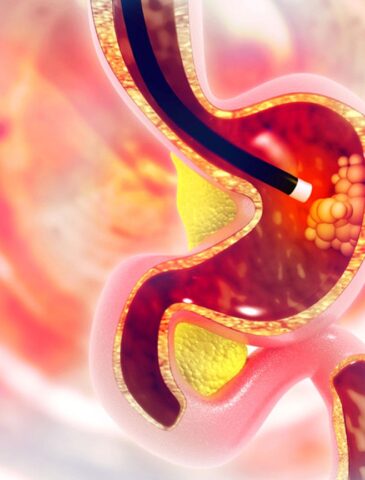

GI endoscopy is a minimally invasive, non-surgical procedure that allows a gastroenterologist to directly visualize and evaluate the digestive tract using a flexible, thin tube equipped with a high-definition camera. This advanced procedure provides a clear view of the esophagus, stomach, duodenum, small intestine, colon, and rectum, enabling accurate diagnosis of various digestive disorders.

One of the key advantages of GI endoscopy is that it is both diagnostic and therapeutic. This means that while identifying the source of a problem, such as an ulcer, inflammation, polyp, or tumor, the specialist can often perform immediate treatment during the same procedure. This dual capability makes GI endoscopy a highly effective and efficient tool in modern gastroenterology.

Upper GI endoscopy focuses on the upper digestive tract, including the esophagus, stomach, and the duodenum (the first part of the small intestine). It is particularly useful for:

During the procedure, if a problem is detected, the gastroenterologist can take biopsies, remove small polyps, or stop bleeding immediately using specialized tools inserted through the endoscope. This eliminates the need for additional surgeries in many cases, making it both safe and convenient for patients.